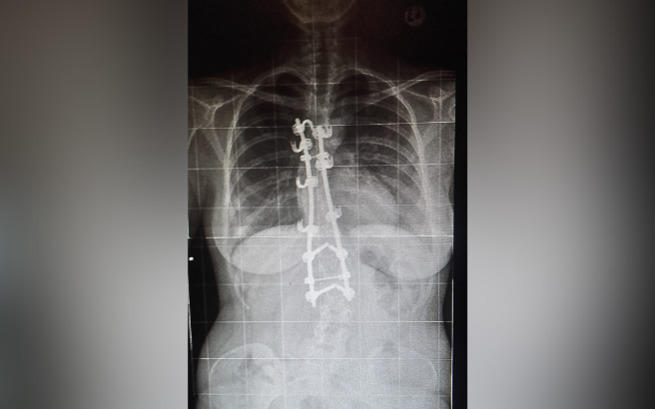

W styczniu 2014 roku byłam operowana. Operacja miała na celu wyprostowanie skoliozy przy pomocy prętów, haków oraz śrub. Niestety, nie wszystko się powiodło. Operacja miała odmienić moje życie, ale nie w taki sposób...

Rozwiązaniem w moim przypadku miałaby być operacja. Tym razem polegająca na usunięciu instrumentarium z kręgosłupa. Jestem gotowa zrobić wszystko, aby się uwolnić. To jednak nie jest takie proste.